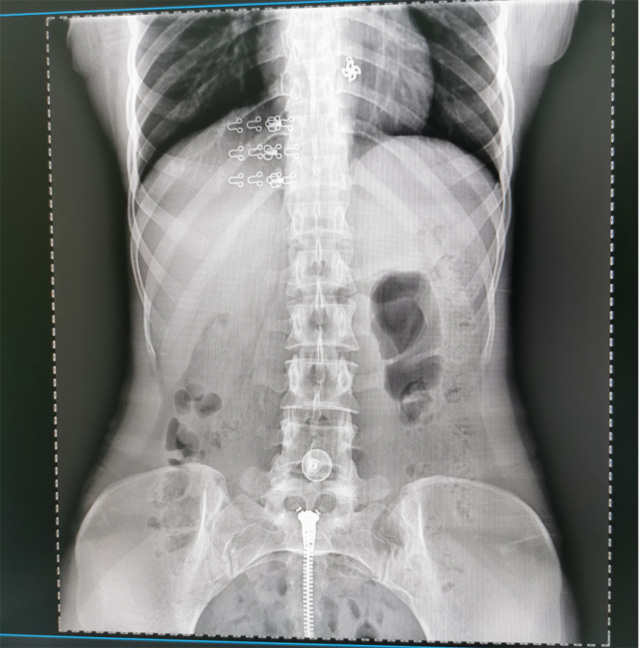

懸吊DR數(shù)字化攝影圖像質(zhì)量高輻射量少誤差小滿足疾病的臨床診斷

提高醫(yī)院的影像科的醫(yī)療服務(wù)水平,滿足滿足人民群眾不斷增長(zhǎng)的醫(yī)療需求,促進(jìn)醫(yī)療技術(shù)快速發(fā)展。醫(yī)院都引進(jìn)懸吊DR拍片設(shè)備新一代數(shù)字化X線攝影系統(tǒng)。標(biāo)志著醫(yī)院的診療水平又上升一個(gè)新的臺(tái)階。懸吊DR滿足人體頭部、胸部、腹部、腰椎、四肢等部位的數(shù)字?jǐn)z影檢查,可以檢查呼吸系統(tǒng)疾病,心臟系統(tǒng)的疾病、骨關(guān)節(jié)系統(tǒng)的疾病,子宮輸卵管造影、胃腸道造影,.有職業(yè)病體檢篩查塵肺病功能。通過(guò)DR數(shù)字化攝影,分段連續(xù)、重疊采集數(shù)字化圖像,利用軟件對(duì)圖像進(jìn)行拼接的方式來(lái)獲得全脊柱、全上肢或全下肢的圖像。新設(shè)備的圖像更清晰,臨床拍攝避免患者再次搬運(yùn)和移動(dòng)產(chǎn)生的痛苦,是創(chuàng)傷骨折患者的福音。輻射減少受照劑量50%,后處理能力強(qiáng)、圖像質(zhì)量高。有效降低操作難度,縮短工作流程,尤其適合大批量體檢。

具有射線劑量小、圖像清晰度高、誤差小等特點(diǎn),懸吊DR已廣泛應(yīng)用于各級(jí)醫(yī)療機(jī)構(gòu)的體檢中心,越來(lái)越受到臨床醫(yī)生的肯定和患者的青睞。為臨床診斷工作提供更加直觀有效的技術(shù)支持,大大提高了患者就醫(yī)效率從而為患者提供更加優(yōu)質(zhì)的醫(yī)療服務(wù)。提高了其成像質(zhì)量和臨床應(yīng)用價(jià)值,并極大減少了受照輻射劑量。有效滿足了各種常見疾病的臨床診斷和治療需求。以醫(yī)療質(zhì)量為根本,以優(yōu)質(zhì)服務(wù)為導(dǎo)向,竭誠(chéng)為人民群眾的健康保駕護(hù)航。